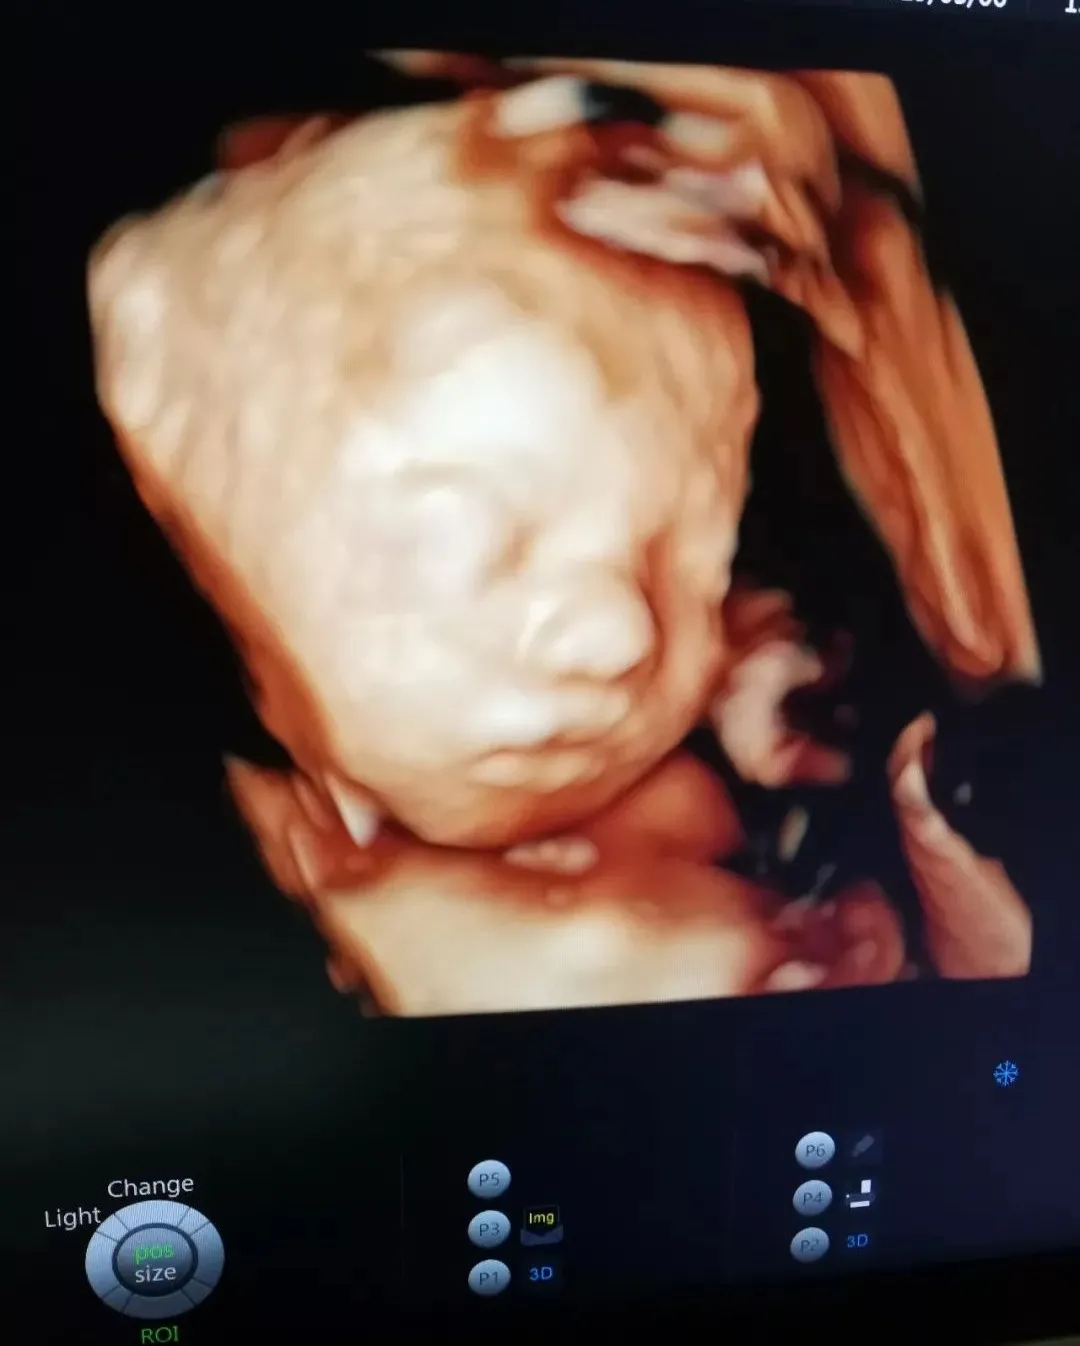

也许肚子里的宝宝

还不能说TA们对妈妈的爱

但通过美琳达的四维彩超画面中

TA们的活泼好动,萌萌的表情

已经说明了一切

胎宝一次次胎动在告诉我们

世界最珍贵的东西

不必费力寻找

一直在我们身边

你好宝贝

你好妈妈

很高兴即将遇见你